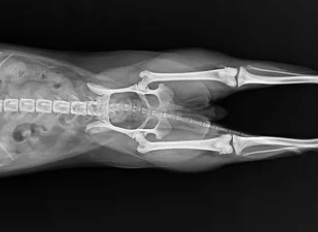

- 촉진 검사: 수의사가 무릎을 만져서 슬개골 움직임 확인

- X-ray 검사: 관절의 틀어짐, 연골 손상, 뼈 변형 여부 확인

- 보행 분석: 탈구 단계와 통증 정도 평가